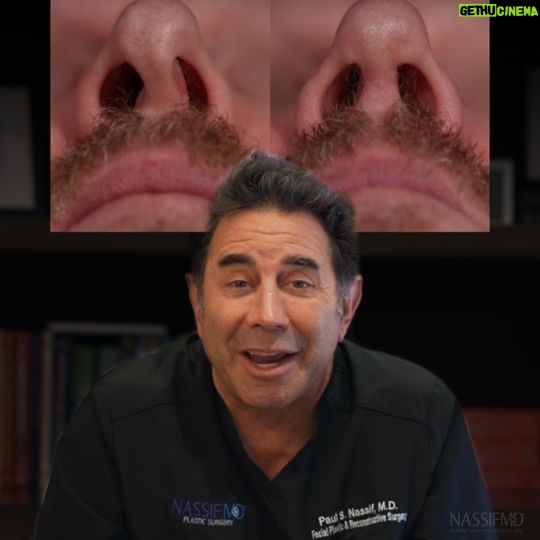

21.2K Likes – Paul Nassif Instagram

Caption : Who remembers Shelley from the Mid-Season Finale of Botched?! Here is a before and after of her results, which ended up being one of the most incredibly complex cases and heartfelt stories we’ve ever had on the show. Shelly had a rare form of skin cancer that led to multiple, horrific complications, which included a gaping hole in the side of her nose. Morpheaform basal cell carcinoma, which Shelley had, is an extremely rare form of the skin cancer I had. It can be a fast-growing basal cell that occurs underneath the skin. In order to help her, we had to perform numerous surgeries, including the need to make a forehead flap! For more on Shelley’s incredible story, watch Botched Season 8, Episode 10: Doctor Nose Best on E! Trusted with Noses Worldwide® _____________________________________________ ☎️ Call us at: 1 (310) 275-2467 💌 Email us at: [email protected] #botched #rhinoplasty #revisionrhinoplasty #nosejob #rinoplastia #rinoplasti #septoplasty #nosesurgery #plasticsurgeon #rhinoplastyspecialist #cosmeticsurgery #transformation #revisionhinoplasty #revisionseptoplasty #morpheaform #basalcell #carcinoma #rhinoplastybeforeandafter #beforeandafter #facialplasticsurgery #rhinoplastydiary #bhfyp #transformationtuesday #ttLikes : 21221